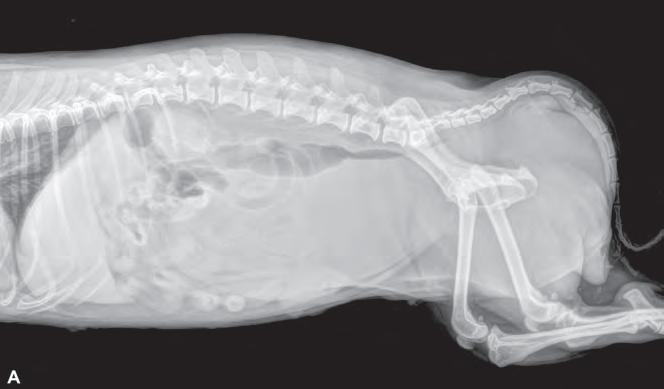

ocupa, además de las radiografías postoperatorias realizadas tras la cirugía correctiva y las efectuadas antes de retirar los implantes, se realizó una TC de revisión tras la extracción de los mismos (al año y dos meses de su colocación), observándose en 3D una buena remodelación y alineación de los huesos. Si comparamos estas imágenes de TC con las primeras, es decir, con las de la planificación quirúrgica antes de la corrección, se puede observar que la superposición de ambas TC muestra una alta precisión en lo que respecta al resultado obtenido (Fig. 8).

Figura 8. (A) Reconstrucción en 3D de los huesos del antebrazo afectado antes de realizar la ostectomía y colocar los implantes y (B) después de retirarlos.